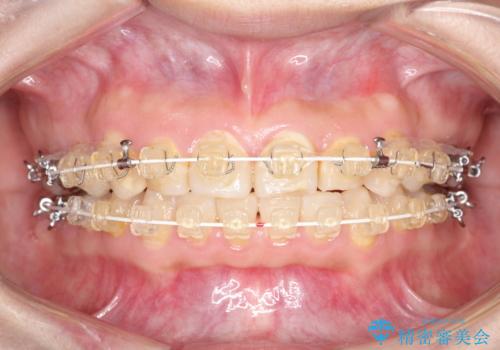

- 矯正装置

- 審美装置

- 2年9ヶ月

- 10-30回